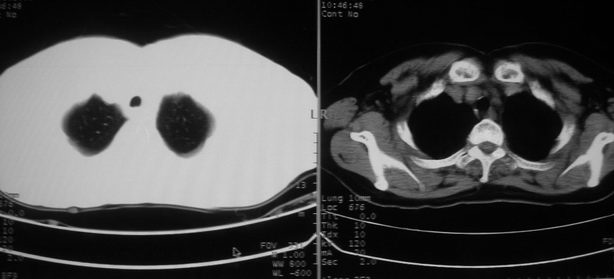

以下是引用zhangzhongshou在2008-5-22 12:51:00的发言:[br]左肺上叶肺癌并左侧胸腔积液可能性大。

以下是引用w_jianhua在2008-5-22 12:59:00的发言:[br]1.左肺上叶肺癌并左侧胸腔积液可能性大。2不除外支气管内膜结核并包裹性胸腔积液,建议支气管镜检3.左肺下叶肺大泡,肺气肿